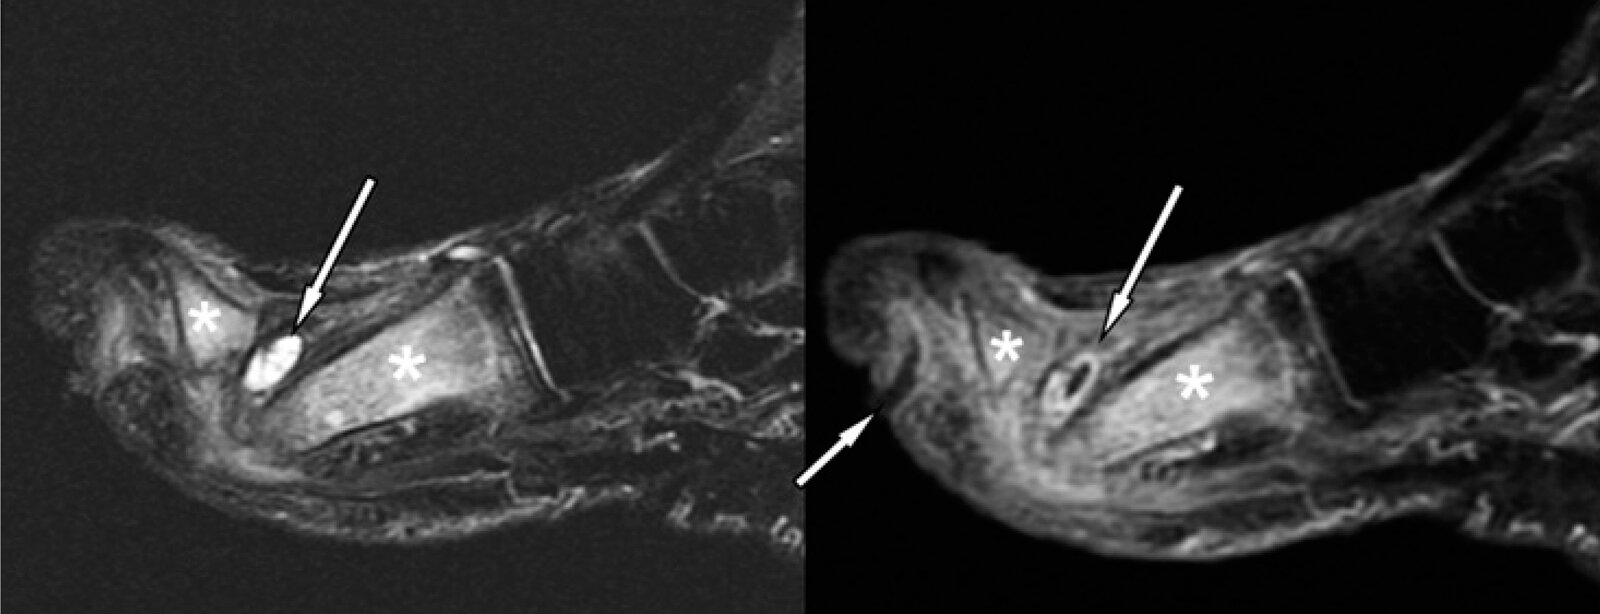

Diabetic neuropathic arthropathy (Charcot foot) [14]

• Neuropathic arthropathy is the development of bone destruction, subluxation/dislocation, and deformity secondary to neuropathy (most commonly diabetic neuropathy).

• The tarsus and tarsometatarsal joints are most commonly affected.

• Clinical presentation depends on the stage.

• Chronic stage: painless bony deformities, midfoot collapse (rocker-bottom foot deformity), osteolysis, fractures

• Diagnosis requires x-ray (first line) and MRI (in diagnostic uncertainty).

• Initial treatment is conservative (mechanical offloading, treatment of diabetes); surgery is used for severe or refractory cases.

Diabetic neuropathic arthropathy can be challenging to distinguish from diabetic foot osteomyelitis; in diagnostic uncertainty, consider bone biopsy. [3]